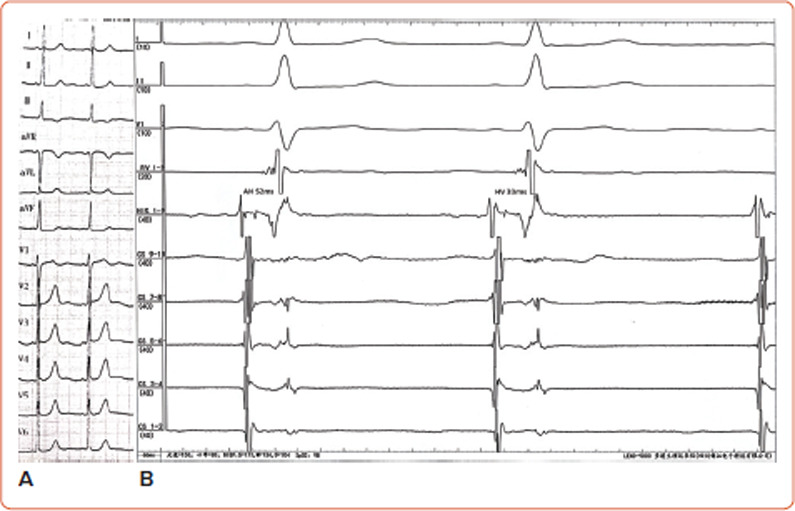

Fasciculoventricular accessory pathways (FVAPs), once considered rare variants of pre-excitation syndrome, are now recognised as ubiquitous in both humans and murine. Nonetheless, most FVAPs are likely electrically silent. However, they can become evident, as reported for some glycogen storage diseases (such as Danon disease and PRKAG2) and during high-voltage septal pacing. Typically, FVAPs only exhibit antegrade and non-decremental conducting properties. A block at the FVAP results in a normal His-to-ventricle interval and a narrow QRS complex without signs of pre-excitation. Decremental conduction over FVAP was once reported in a setting of PRKAG2 mutation. However, in the present case, incremental atrial pacing revealed varying His-to-ventricle intervals, with functional decremental conduction that was accompanied by varied QRS morphologies. These findings underscore the diagnostic challenges posed by FVAPs, and highlight the need for meticulous electrophysiological assessment to accurately distinguish them from other pre-excitation syndromes. This case exemplifies the nuanced behaviour of FVAPs, emphasising their clinical and diagnostic complexity in electrophysiological practice.